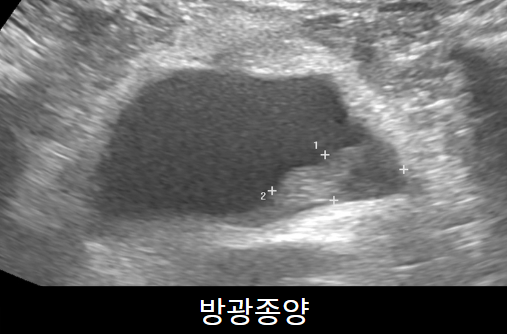

하복부초음파(신장,방광,전립선 초음파)

옆구리,하복부 통증이 있을 때 가장 많이 하는 초음파로 신장낭종, 신장암, 신장결석, 수신증, 방광 내 종양, 전립선비대 등을 확인할 수 있습니다. 전 소요시간은 약 10분입니다.